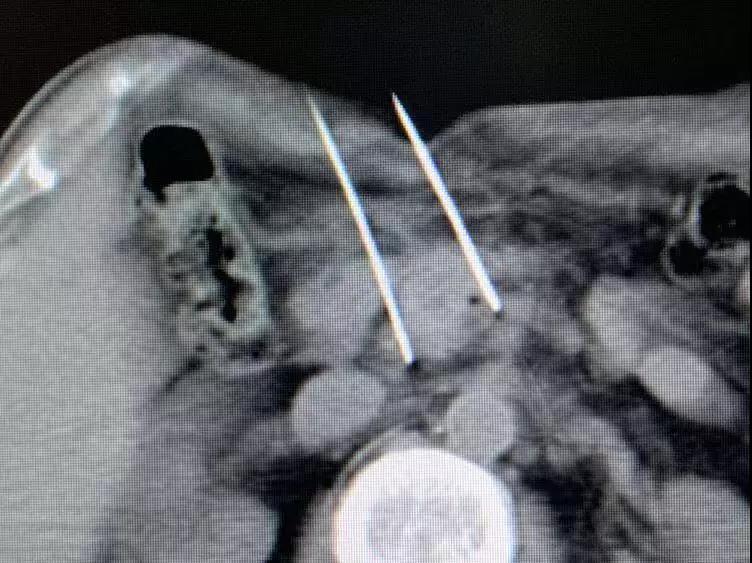

Необратимая электропорация при опухоли поджелудочной железы

Для дальнейшего лечения как можно скорее его сын привез его в Онкологическую больницу Фуда 31 августа. После обследования ему был поставлен диагноз несоциализированная аденокарцинома III стадии в поджелудочной железе и диабет II типа с множественными узлами в печени, легких и щитовидной железе. После обсуждения с доктором Ню Личжи и медицинской командой он и его семья согласились провести катетеризацию в подключичной вене 6 сентября и на сдедующий день необратимую электропорацию при опухоли поджелудочной железы. После интенсивной терапии его состояние улучшалось с каждым днем.